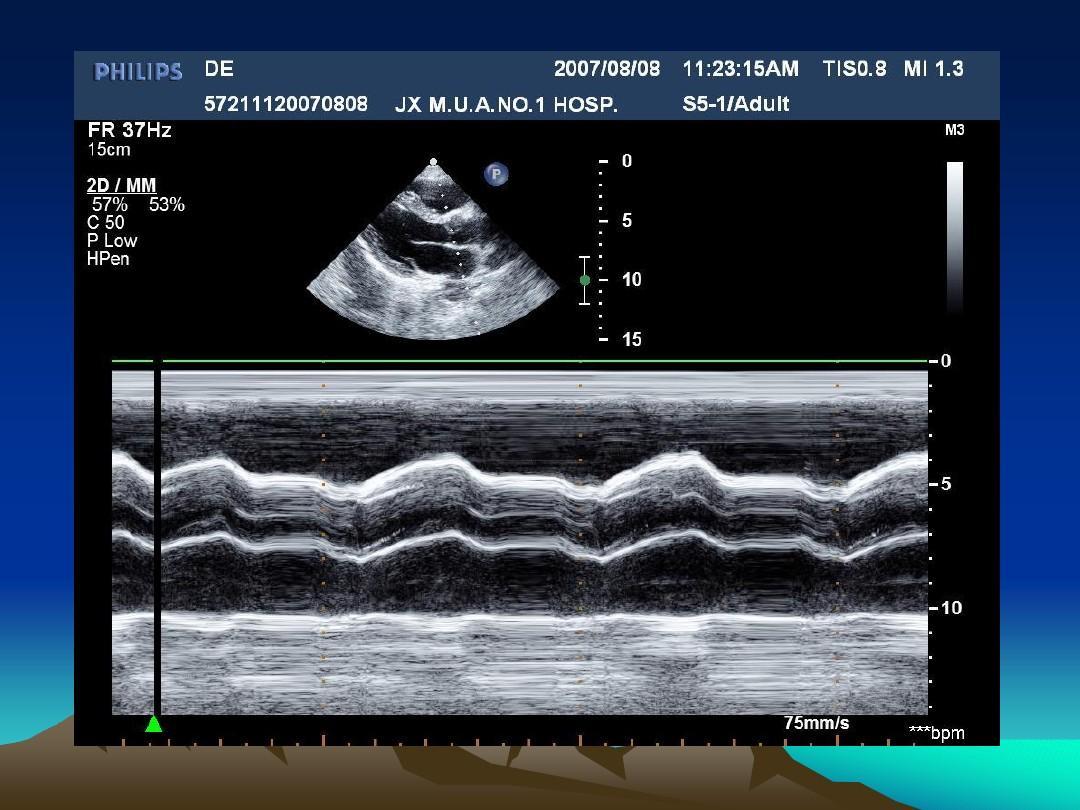

(2) 在急性心肌梗死应用上用超声心动图却有明显风险。所以说在寻求特异性较强的生化指标就变得至关重要了。

因为BNP在心室起源,有着释放量与心功能不全程度存在一定比例关系,所以就说在诊断心功能异常方面BNP有着它不一样的优势。在诊断心肌梗死后心功能不全上用不同的方法结果也是有区别的,在敏感性上,分别为(1)血浆BNP(84%);

(2)超声心动图(82%.);(3)临床检查(64%);(4)临床症状诊断(46%)。这也就是在诊断心肌梗后心功能不全上BNP是它的重要敏感指标。